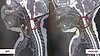

– Мы начали обследование с поиска генетической патологии, в том числе спинальной мышечной атрофии, но диагнозы не подтвердились. Пациентке была выполнена магнитно-резонансная томография, в ходе которой наши высококлассные рентгенологи нашли довольно редкую патологию – врожденную арахноидальную кисту шейного отдела позвоночника. Это доброкачественное образование, стенки которого выстланы паутинной оболочкой спинного мозга. Всего мы нашли 14 случаев такой патологии в англоязычной литературе. Самому маленькому пациенту с таким диагнозом было 2 года, нашей девочке – всего три месяца. Мы оценили свои возможности и приняли решение, что будем оперировать, – рассказал нейрохирург Кировской областной детской клинической больницы Эдуард Сырчин.

По данным МРТ из-за образования спинной мозг маленькой пациентки был истощен до 1 миллиметра, когда в норме должен составлять порядка 6-7 миллиметров. Врачи детской областной больницы провели ювелирное оперативное вмешательство. Была вскрыта и дренирована полость кисты. Сложность заключалась в том, что все невральные структуры очень маленькие, и чтобы провести операцию специалисты использовали увеличительную технику и инструменты толщиной всего 2 миллиметра. Киста располагалась перед спинным мозгом, что затрудняло процесс оперативного вмешательства, врачам было важно не повредить все окружающие структуры, чтобы в будущем у малышки не было осложнений.